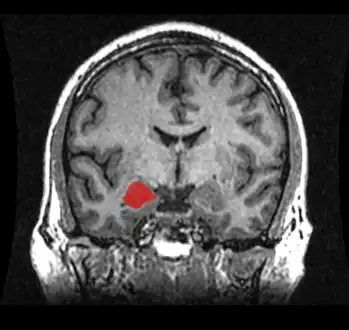

T1 weighted MRI scan of a normal coronal section of human brain with amygdala marked in red.